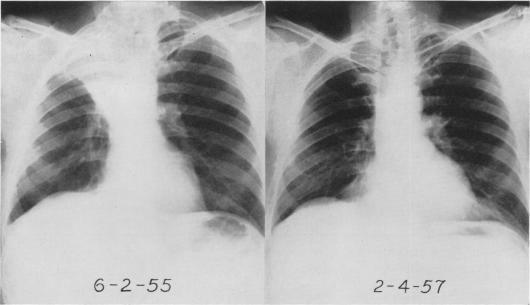

PAULSON D L, SHAW R R

Ann Surg. 1960 May;151(5):729-40. doi: 10.1097/00000658-196005000-00013.